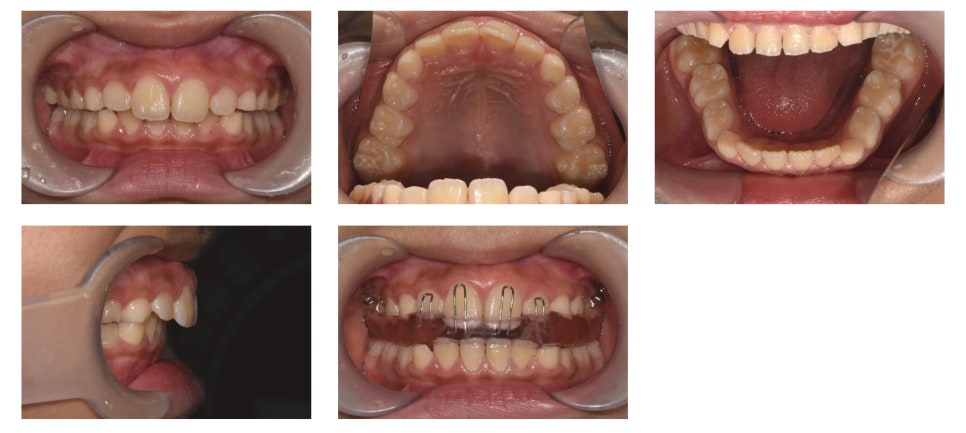

유지 장치 착용 5개월 후 구내 사진 및 activator 장착 사진

약 5개월간 유지 장치를 착용한 후의 구내 사진입니다.

상악 전치부가 하악 전치부에 비해 많이 튀어나와 있는 부분은 아직 교정되지 않은 상태였습니다.

이를 개선하기 위해 하악골 성장을 촉진시키는 activator 장치 착용을 시작했습니다.